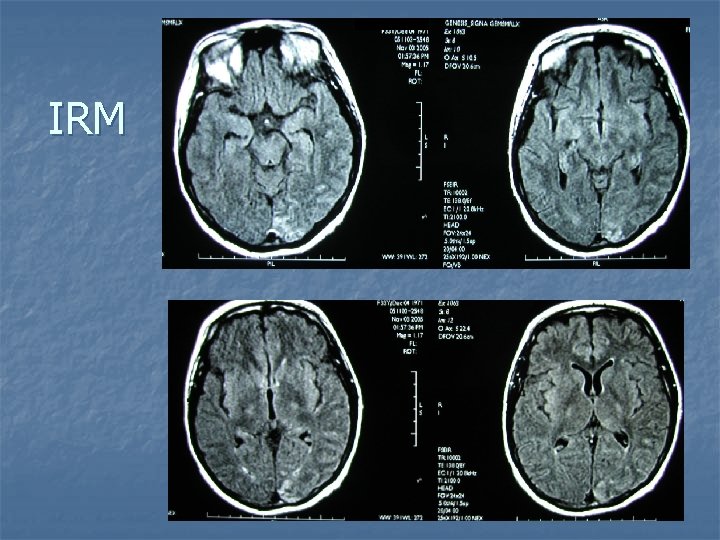

IRM

Diagnostic n n IRM cérébrale : hypersignaux Flair du cortex pariéto-occipital gauche compatible avec une encéphalopathie aigue hypertensive FO normal